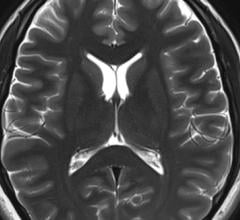

Nov. 19, 2025 — Royal Philips has announced an extended partnership with Cortechs.ai. Together, the companies will ...